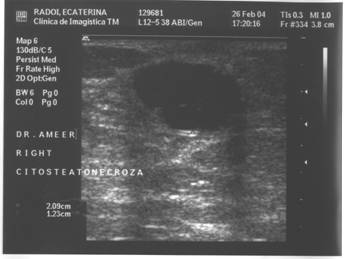

CITOSTEATONECROZA